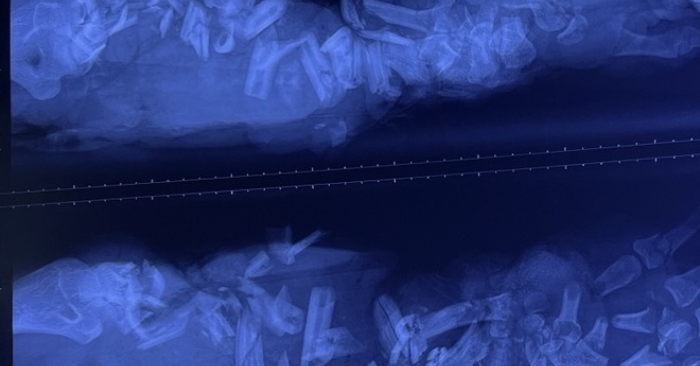

Bệnh nhân nhập viện tại Bệnh viện Chấn thương Chỉnh hình vào khoảng 5 giờ sau tai nạn. Thời điểm này, các bác sĩ ghi nhận vết thương dập nát phức tạp kéo dài từ cẳng tay đến bàn tay trái. Nhiều đoạn xương cẳng tay bị gãy vụn thành nhiều mảnh nhỏ, cấu trúc giải phẫu bị phá hủy nghiêm trọng. Mô mềm xung quanh tổn thương nặng, sưng nề, tím tái, vết thương nhiễm bẩn do dính nhiều đất cát, dầu nhớt từ máy móc công nghiệp.

Các bác sĩ cho biết, việc bệnh nhân đến viện muộn khiến nguy cơ nhiễm trùng, hoại tử và biến chứng toàn thân tăng cao. Qua thăm khám lâm sàng và đánh giá hình ảnh học, ê-kíp điều trị nhận định các mạch máu, thần kinh và gân cơ vùng cẳng tay đã bị tổn thương gần như hoàn toàn, không còn điều kiện để tái tạo hay nối chi.